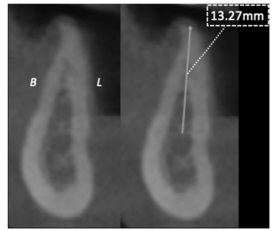

A partir da imagem e das informações precedentes, julgue o item a seguir.

A imagem apresentada permite a seleção do implante dentário e, em especial, sua extensão, considerando-se a proximidade com áreas anatômicas de risco e o baixo perfil de distorção dimensional existente nas tomografias de feixe cônico em torno de 10% da imagem real.

A reconstrução axial dos arcos dentários oferece a possibilidade de análise da distribuição de implantes, conforme a configuração do padrão de crescimento mandibular, sendo maior a quantidade de implantes para o arco em forma de U invertido.

Um parâmetro determinante para o comprimento do implante é a proporção coroa-implante, para o qual a biomecânica mais favorável consiste no comprimento da coroa menor que o do implante.